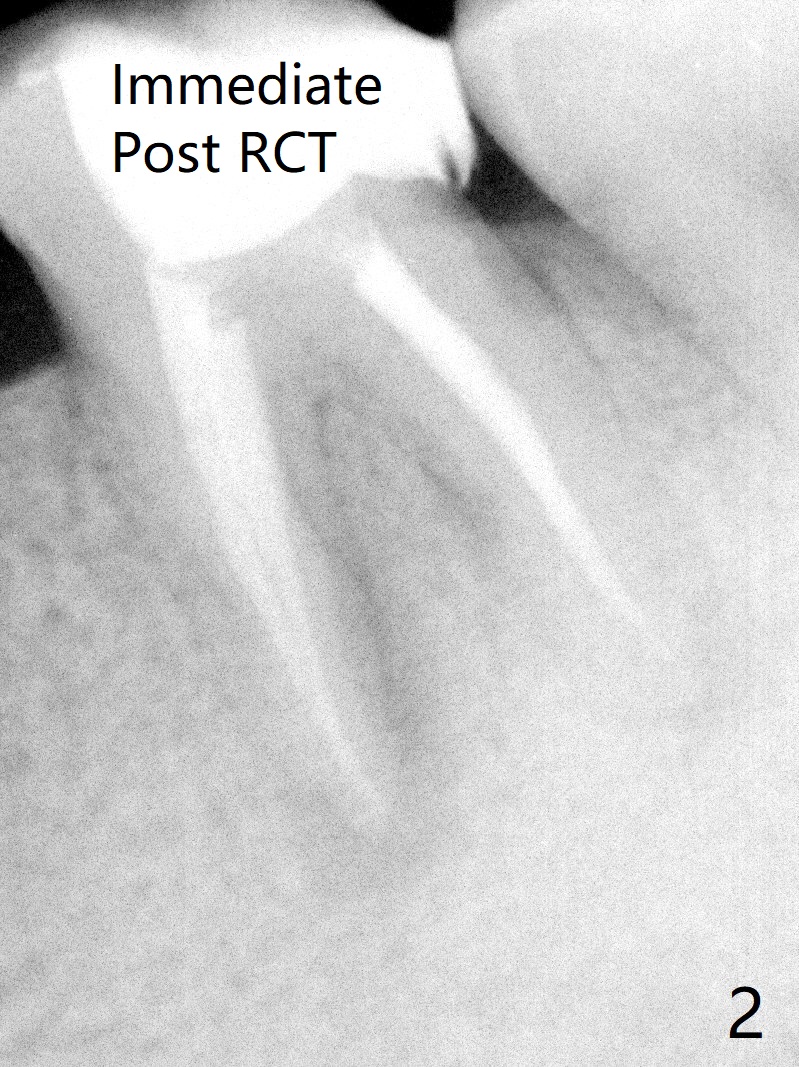

A 29-year-old man has chronic apical perio-dontitis at #19 (Fig.1) for 5 years before RCT with apical buccal swelling (Fig.2). Three days post RCT a fistula develops (Fig.3); curettage is performed. Crown is prepared 3.5 years later (Fig.4). Bitewing is taken immediately before cementation (Fig.5). There is no leakage 2 years 8 months post cementation (Fig.6,7) or periapical radiolucency 6 years 3 months post RCT (Fig.8). Return to Professionals Xin Wei, DDS, PhD, MS 1st edition 11/27/2019, last revision 11/28/2019